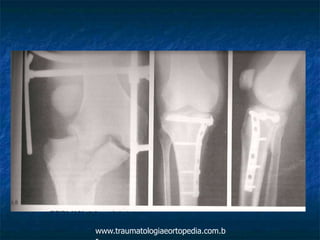

 Lesões do tipo V e VI: redução indireta por meio

de distrator, fixação e uso de enxertos. Pode se

combinar duas placas, ou fixação interna e

externa, ou usar fixador externo híbridos.

www.traumatologiaeortopedia.com.b